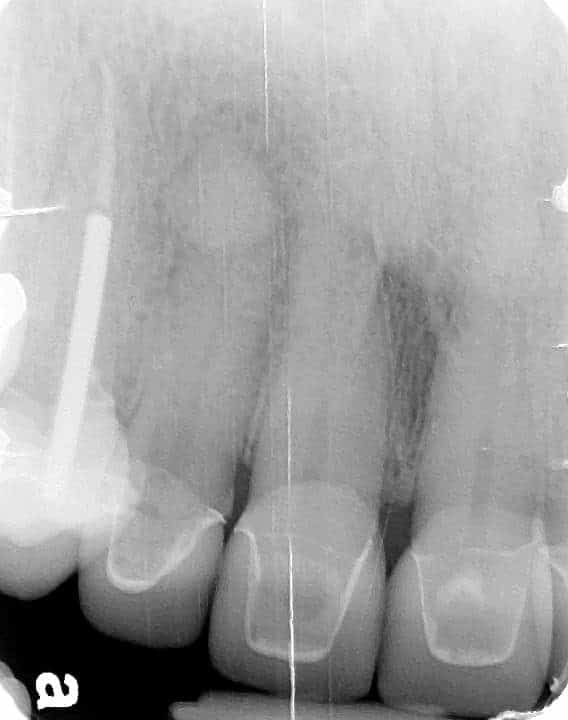

Below is a case of full arch same day temporization using the socket shield , root submergence and pontic shield techniques to preserve the site architecture . Neodent GM implants were placed in a guided fashion and same day temporization was performed using a milled PMMA.